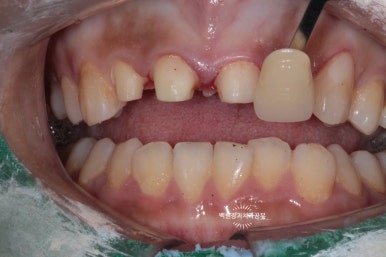

해당 치아의 삭제가 완료되었습니다.!!

치아가 많이 없어져 보여서 속상합니다..

다만 최종 지르코니아 크라운이 최소 2mm 정도의 두께를 얻으려면 이 정도의 삭제는 필수입니다. 더 얇으면 지르코니아 크라운.. 얼마 쓰지 못하고 깨져요!!... 본 환자분의 경우 인접한 면에도 충치가 많이 있었기에 크게 손해보는 상황은 아니었습니다.

눈치 채셨을런지 모르겠지만, 왼쪽 위 송곳니도 레진치료를 해드렸습니다.!!

약간 색상의 차이는 느껴지지만, 훨~씬 좋아진 모습을 보이고 있어요.

위 아래 치아가 교합이 된 상태에서 치아의 삭제량을 다시 한 번 체크합니다.

아주 최소한으로만 삭제가 되었고, 아래 앞니도 조금은 다듬어 주어 지르코니아 크라운의 자리를 확보해줍니다.

좌우로 그리고 앞뒤로 아래턱을 움직여보면서, 크라운이 제작될 공간이 있는지 반드시 확인해야합니다.